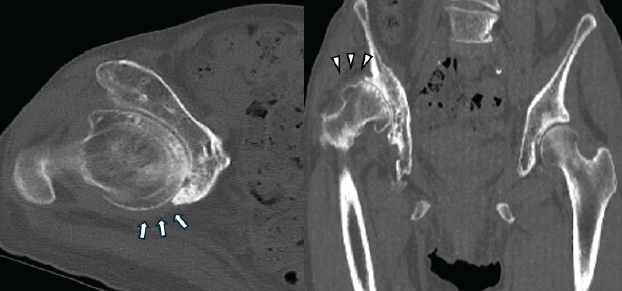

Computed tomography revealed a severely deformed acetabulum, manifested by excessive anterior over coverage, a posterior wall deficiency, and a bone defect in the superior weight-bearing region of the acetabulum (Fig. 2).

Figure 2: Pre-operative computed tomography images (left, axial view; right, horizontal view). The axial view shows excessive anterior acetabular coverage and a posterior wall defect (arrows). The horizontal view shows a severe bone defect in the superior aspect of the acetabulum, corresponding to the weight-bearing region (arrowheads).